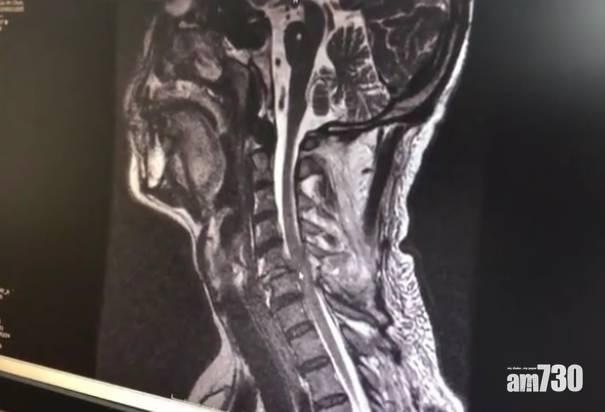

劉男頸椎骨折。(互聯網)

出名魯莽、愛做傻事而被內地民眾戲稱為「二哈」(「二」意為「傻」)的哈士奇(港稱「雪橇犬」),農曆新年期間又有「壯舉」!湖南永州新田縣一戶姓劉人家大年初五外出拜年後回家,剛走到家樓下,67歲的男戶主就被從天而降的雪橇犬撞暈。眾人見狀立即送劉男入院,之後劉男被轉送至郴州市第一人民醫院脊柱外科救治。該院姓童醫生表示,雪橇犬擊中劉男後頸,導致其頸椎骨折脫位、脊髓損傷,需動手術治療,預計完全恢復需時3個月至半年。童醫生還稱,「我還從來沒有見過因為被狗砸倒造成這樣的傷情」。